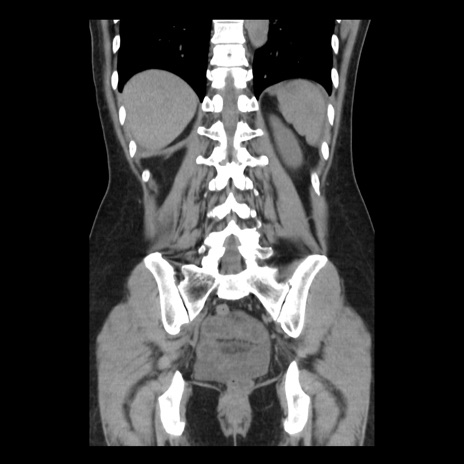

症例10(冠状断像)

【症例】 50歳代女性

【主訴】 腹痛

【現病歴】前日生レバーを食べた。今朝に排便あり。 昼前に突然発症の腹痛を生じ、当院救急外来を受診した。

【既往歴】 子宮筋腫にてで子宮全摘後

【身体所見】 意識清明、腹部:平坦、軟、下腹部やや左を中心に圧痛・反跳痛あり、筋性防御あり

【データ】WBC 7800、CRP 0.07